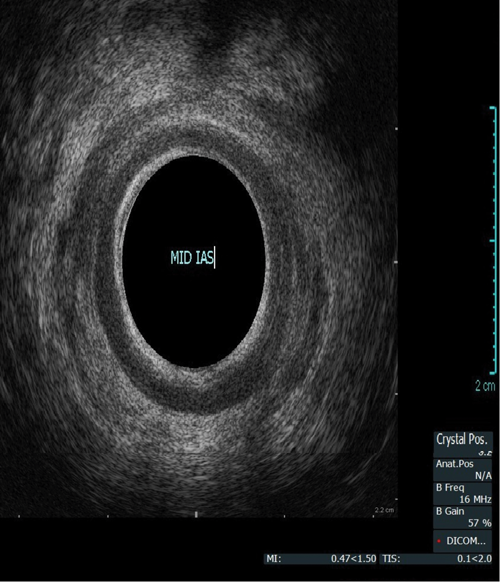

This procedure is indicated for assessment of the anal sphincter in patients with incontinence. This allows evaluation of the internal and external anal sphincters (sphincter thickness, length and scarring). It is pertinent to obtain history of obstetric trauma as well as any surgeries / intervention to aid assessment.

As with the proctogram technique, the procedure is explained in detail and consent obtained prior, and the presence of a chaperone makes the patient more comfortable. Digital rectal examination is performed as a reference to assess anal tone. Still images as well as cine of the ultrasound are taken to assess the sphincter complex (Figure 3).

Figure 3a: (Top, middle and bottom) Normal endoanal ultrasound.